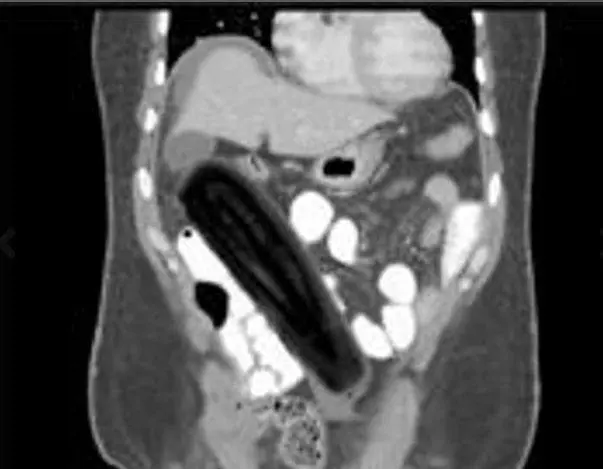

Pazze radiografie: gli oggetti che possono finire nel corpo umano

Oggetti bizzarri che hanno trovato la loro strada all'interno del corpo umano, e documentati grazie alle pazze radiografie raccolte dal dottor Frank Gaillard. Quest’ultimo ha fondato Radiopaedia.org, un sito collaborativo che raccoglie casi radiologici e articoli medici a tema.